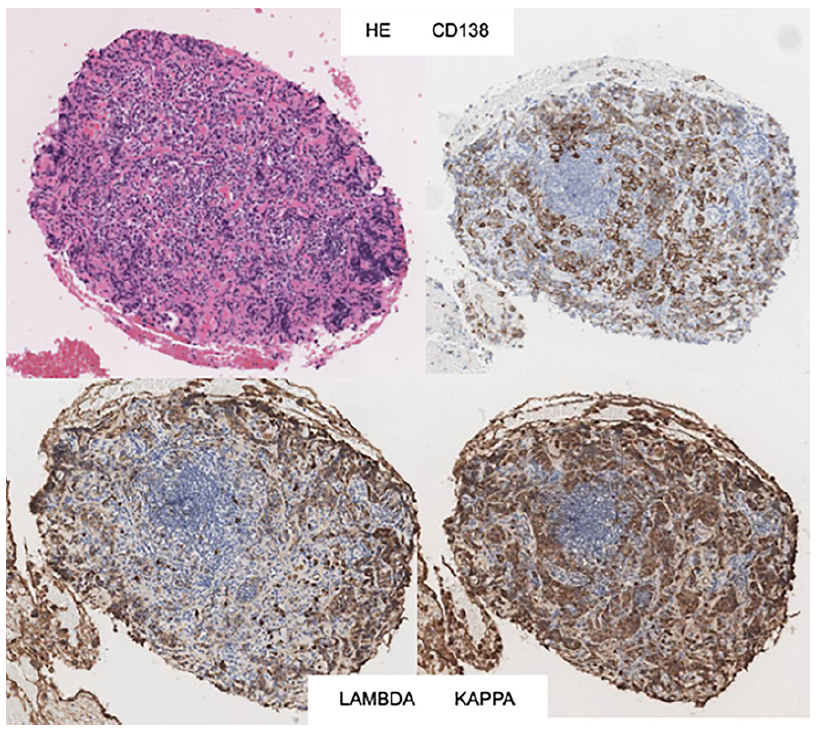

We present a 71-year-old female with no relevant past medical history. The patient was started on a proton pump inhibitor for dyspepsia, with complete symptomatic improvement. One year later, there was symptom recurrence with weight loss. Upper endoscopy revealed a 10 cm gastric subepithelial lesion, with central erosion (Fig. 1). Pathology evaluation was negative for malignancy. Computed tomography showed an extensive gastric wall lesion, with no adenopathies (Fig. 2). Endoscopic ultrasound (EUS) evaluation revealed an 8 cm subepithelial polycyclic hypoechoic lesion, with transition zone suggestive of the third/fourth layer origin (Fig. 3a). Quantitative elastography evaluation showed strain histogram 68 (Fig. 3b). The fine needle biopsy using a 22-G Franseen needle revealed clonal proliferation of plasma cells, positive for CD45/CD138 and negative for CD3/CD20/CD56 (Fig. 4). There was no anemia, hypercalcemia, or kidney impairment, and no abnormalities were found on bone marrow biopsy and myelogram apart from mildly increased plasma cell proliferation (5-10% of total cells). The positron emission tomography/computed tomography scan showed increased gastric uptake, with a maximum standardized uptake value of 3.3. Treatment consisted of surgical resection and the patient had an uneventful postoperative course. The surgical specimen confirmed the diagnosis.

Fig. 4 Histopathology examination showing clonal proliferation of plasma cells, positive for CD45/CD138 and negative for CD3/CD20/CD56.

Solitary extramedullary plasmacytomas are plasma cell tumors arising outside of the bone marrow, accounting for approximately 3% of plasma cell malignancies [1]. Within this category, gastric plasmacytoma accounts for less than 2% of extramedullary plasmacytomas [2]. They frequently present as solitary lesions, although sometimes the endoscopic appearance can only reveal erosion of the mucosa [3]. Symptoms are nonspecific, with epigastric discomfort, abdominal pain, nausea, and vomiting commonly reported. Diagnosis requires biopsy-proven extramedullary tumor with evidence of clonal plasma cells, with flow cytometry immunophenotyping assuming a major role in most hematologic malignancies, along with normal skeletal and bone marrow survey and the absence of endorgan damage attributable to the underlying plasma cell disorder [4]. The role of EUS is not standardized, and data are scarce regarding EUS features of a gastric plasmacytoma [5]. Surgery is usually the treatment of choice, with a good prognosis [6]. The authors highlight the EUS role as part of the diagnostic workup of gastric plasmacytoma, a rare clinical entity.